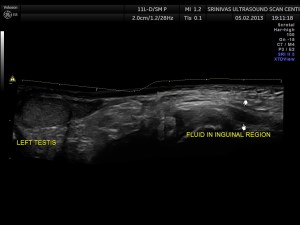

This was a 11 year old boy referred for evaluation of left inguinal swelling on and off.

The clinical diagnosis was bubunocele.